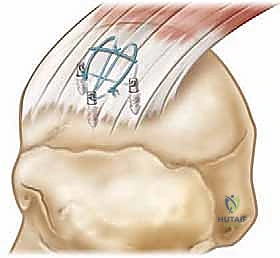

هنا ظهرت تقنية مزدوج الصفوف (Double-Row). تعتمد هذه التقنية الهندسية الحيوية على استخدام صفين من الخطاطيف العظمية (Anchors):

1. الصف الداخلي (Medial Row): يُزرع في حافة الغضروف المفصلي.

2. الصف الخارجي (Lateral Row): يُزرع في الحافة الخارجية لعظمة العضد.

يتم تمرير الخيوط من الصف الداخلي عبر الوتر، ثم تُسحب وتُثبت في الصف الخارجي. النتيجة؟ يتم ضغط الوتر الممزق بالكامل وبشكل مسطح ضد "البصمة العظمية" (Footprint)، مما يزيد من مساحة التلامس بين العظم والوتر بنسبة تصل إلى 200% مقارنة بالصف الواحد. هذا الضغط المحكم يخلق بيئة مثالية لالتئام بيولوجي قوي ومستدام، ويمنع تسرب السائل المفصلي بين الوتر والعظم.

- الصف الداخلي: تُزرع مثبتات عظمية دقيقة (Anchors) محملة بخيوط جراحية فائقة القوة في الجزء الداخلي من البصمة العظمية.

- تمرير الخيوط: تُمرر هذه الخيوط عبر نسيج الوتر الممزق باستخدام أدوات دقيقة.

- الصف الخارجي: تُسحب الخيوط لتغطية الوتر فوق العظم، ثم تُثبت باستخدام مثبتات عظمية أخرى في الجزء الخارجي، مما يخلق شبكة محكمة تضغط الوتر بقوة ضد العظم.